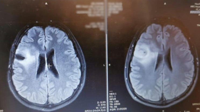

Lifestyle image By TalkerUpdated Aug 6, 2025 Scott Hinch's brain scans. (Brain Tumour Research Charity via SWNS)